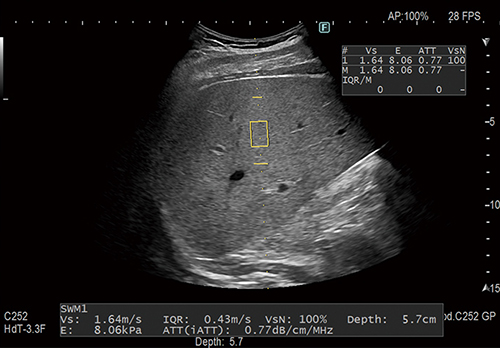

肝疾患の診断をサポートする

Shear Wave Measurement/iATT搭載(オプション)

組織にせん断波を発生させ,伝搬速度(Vs)を計測することで硬さを評価できます。肝脂肪化の程度を推定するための指標(ATT)も同時に計測します。